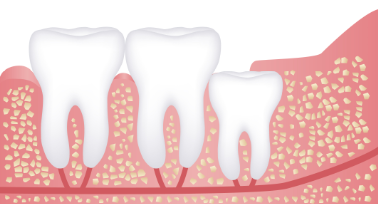

사랑니는 우리 입속에 가장 뒤에 난 어금니를 말하며, 전문용어로 설명해 드리면 제3대구치라고 하며 얼굴을 중심으로 좌우로 8번째 자리하고 있는 치아를 말합니다. 사랑니는 사춘기 이후에 자란다고 합니다. 사춘기에는 여러 가지 감정을 느끼게 되고 그 감정 중 하나가 사랑이라는 감정이지요. 그래서 이 치아를 사랑니라고 부른다고 합니다.